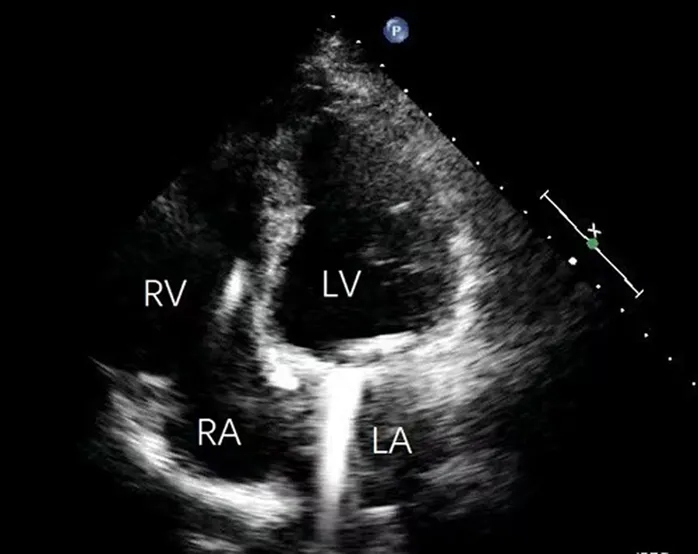

针对心尖部室壁瘤的典型症状,鉴别诊断需重点排除以下常见病因:1)肥厚型梗阻性心肌病:经胸超声心动图显示巨大解剖性心尖前壁室壁瘤,约占左心室容积60%,伴收缩期反常运动,根据该表现排除肥厚型梗阻性心肌病诊断(图1、2);2)冠状动脉疾病:冠脉造影提示未见明显狭窄、心肌桥或血流异常,据此排除冠状动脉相关疾病(图2)。

图1 术前经胸腔超声心动图

图注:Aneu=室壁瘤;LA=左心房;LV=左心室;RA=右心房;RV=右心室;TTE=经胸超声心动图

经胸超声心动图提示:巨大解剖性心尖部室壁瘤,约占左心室容积60%,伴收缩期反常运动(图1);室间隔呈代偿性肥厚,而左心室中段及基底段收缩正常。负荷成像提示:重度人工瓣膜狭窄(峰值流速4.4 m/s,峰值与平均跨瓣压差分别为74 mmHg与41 mmHg),中度二尖瓣反流,左心室射血分数减低(25%)。CTA提示:前壁心尖部存在巨大室壁瘤(图3A、3B);左心室舒张末期容积为184 mL,收缩末期容积为119 mL,射血分数为38%(图3C)。动态心电图监测显示:窦性心律与起搏心律并存,多形性室性早搏,完全性右束支传导阻滞,以及短阵室性心动过速;心室异位激动灶可能起源于前乳头肌根部。